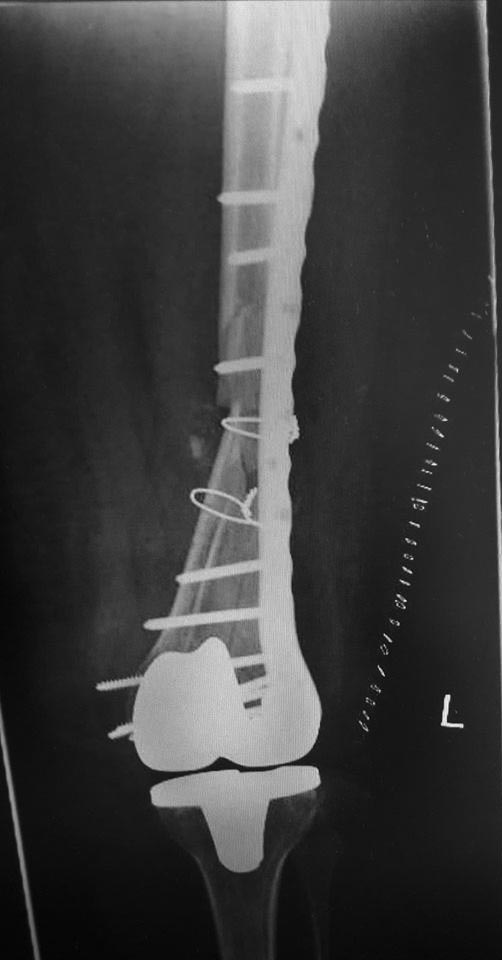

[Ortho] Перипротезный перелом дистального отдела бедра

Как оказалось в нашей ЦРБ сделали уже сегодня шеф решил без СТ. ациент

41 года с большим количеством патологии. То есть полных 76 лет.